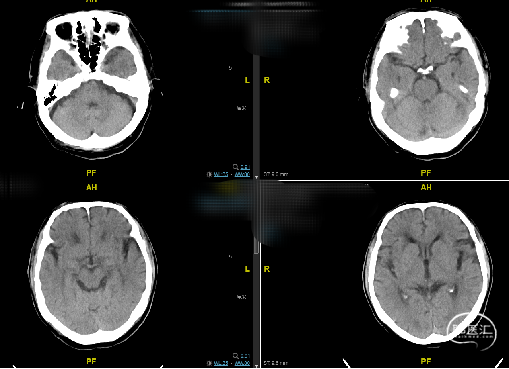

现病史:患者一月余前出现右侧肢体麻木无力,为发作性,持物行走欠稳,无视物模糊、视物旋转,无耳鸣、听力下降,无肢体抽搐强直,13天前于我院神经内科住院治疗,患者右侧肢体无力好转,病程中查彩超及头颈部CTA提示双侧椎动脉开口重度狭窄。

辅助检查(CTA):双侧椎动脉开口重度狭窄,左侧椎动脉为优势动脉,椎动脉颅内段及基底动脉显影良好。

初步诊断:椎动脉狭窄,腔隙性脑梗死,脑动脉粥样硬化,脑梗死后遗症,脑白质病,原发性高血压,心动过缓,腰椎间盘突出,鼻窦炎。

患者左侧椎动脉稍优势,右侧椎动脉开口重度狭窄、次全闭塞,左椎开口重度狭窄。

辅助检查(CTA):双侧椎动脉开口重度狭窄。

患者左侧锁骨下动脉重度狭窄伴斑块形成,左侧椎动脉开口处次全闭塞,右侧椎动脉开口处中重度狭窄,右侧后交通动脉发达。